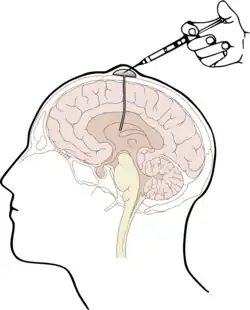

Central nervous system prophylaxis

Central Nervous System Prophylaxis, or CNS prophylaxis, is a type of chemotherapy for patients at risk of cancer metastasis into the central nervous system (CNS).[1] Prophylaxis originated from the Greek word “phulaxis”, meaning the act of guarding.[2] CNS prophylaxis refers to preventative measures that kill cancer cells potentially in the intrathecal space and the organs of the central nervous system.[1]

The most widely-used prophylactic drug is methotrexate (MTX), which is normally administered by one of two methods: intravenous injection (IV HD-MTX) and intrathecal injection (IT-MTX).[1][4] Intravenous injection requires a direct injection of high-dose MTX into a patient’s vein;[4] Intrathecal injection, i.e. injection of the drug into the intrathecal space holding cerebrospinal fluid (CSF), is either administered via the Ommaya reservoir, an implanted container passing fluid into the brain, or by lumbar puncture.[1]

The other solution is intrathecal injection of MTX. One method is by surgically implanting under the scalp an Ommaya reservoir, to be attached to a ventricular catheter leading into the ipsilateral anterior horn. The implant provides long-term access to the cerebrospinal fluid and is used for administration of antimicrobials, antifungals, antineoplastic and analgesic medications.[11] Alternatively, MTX may be injected into the intrathecal space via lumbar puncture. After sterilization and local anesthetic, or general anesthesia in paediatric practice, a needle is used to inject MTX between the L3 and L4 or L4 and L5 vertebrae to avoid damage to the conus medullaris.[12]